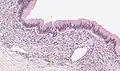

Micrograph showing a mucinous cystadenoma of the ovary. H&E stain.

Microscopy